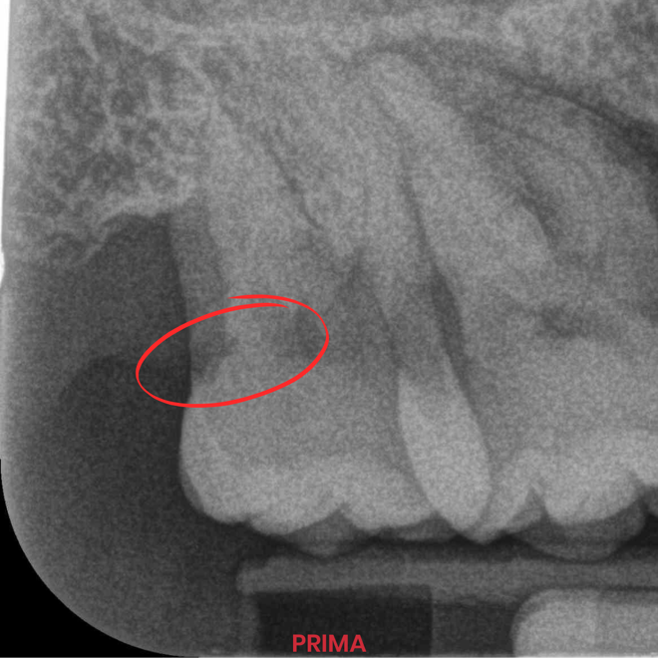

In odontoiatria, le sfide quotidiane richiedono materiali versatili e affidabili. Nel trattare una carie distale sull’elemento 1.7, mi sono trovato di fronte a una condizione critica: l’impossibilità di isolare il campo operatorio con una diga di gomma. Grazie a Stela, composito autopolimerizzante di ultima generazione, sono riuscito a ottenere un risultato impeccabile anche in un ambiente complesso.

Il trattamento di una carie distale su un molare superiore rappresenta già di per sé un ostacolo tecnico significativo. Quando poi il campo operatorio non è isolabile con una diga, il rischio di contaminazione e l’esigenza di un’adesione efficace aumentano notevolmente.

Grazie a Stela, il restauro dell’elemento 1.7 è stato completato con successo senza troppe difficoltà. Ecco i punti chiave del risultato:

Ho potuto notare una rapidità di esecuzione, zero gap a livello marginale, estrema lucidabilità e durezza di superficie del restauro ultimato. Stela ha rivoluzionato il mio modo di lavorare!